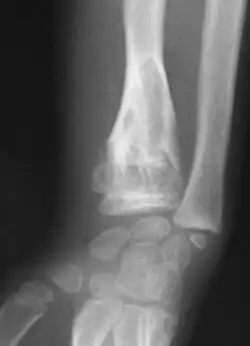

X-ray image showing enchondromas localized in the lower part of the radius of a 7-year-old girl with Ollier disease. | |

Abnormal bone growth such as shortening or thickening and deformity may be observed in patients of Ollier disease. These bone lesions are visible at birth using radiography but are usually not screened or examined for until clinical manifestations present during early childhood. However, some patients may exhibit no signs of any symptoms.[1] One study found thirteen to be the mean age of diagnosis in patients with Ollier disease. In an X-ray, there would normally be the presence of several homogeneous lesions of an oval or elongated shape with bone edges that are slightly thickened.[3] With age, these lesions may calcify and appear as diffusely minute spots or stippled. Fan-like septations or streaks would be indicative of the presence of several enchondromas. Early detection and consistent and repeated monitoring is important in order to prevent and treat any potential bone neoplasms.